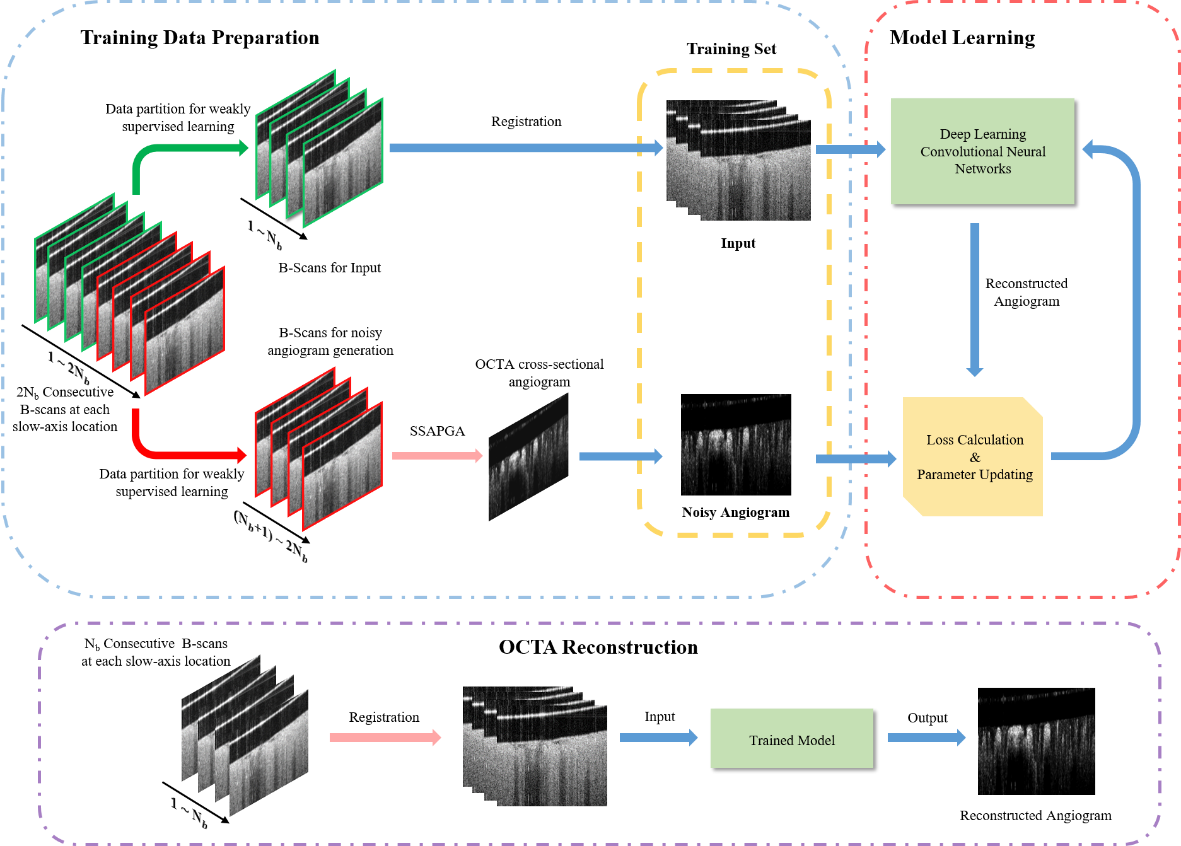

近期,课题组在该领域再度取得新进展,医学影像领域顶级期刊IEEE Transactions on Medical Imaging于2020年11月2日以长文(Regular Paper)形式在线发表了他们题为“Weakly Supervised Deep Learning Based Optical Coherence Tomography Angiography”的研究论文(https://doi.org/10.1109/TMI.2020.3035154),第一作者为任秋实课题组博士后姜喆。该工作提出一种新型的弱监督深度学习OCTA重建算法框架,基于该框架,可以在无需额外提供高质量OCTA标签图像的前提下,实现高效训练网络,获得足以媲美监督深度学习OCTA重建算法的高质量重建图像,为解决标签数据来源问题,以及面向临床需求的问题提出了新的解决方案。

图1. 弱监督深度学习OCTA重建算法框架

研究团队分别利用SD大鼠脑部血管造影数据和健康人眼数据对弱监督深度学习OCTA重建算法框架进行验证。提出的弱监督学习模型在SD大鼠数据集上展示了足以媲美基于高质量标签的监督学习算法的重建质量。不论是在噪声水平、对比度还是血管连续性上,均要明显好于目前最好的解析算法SSAPGA及基于低质量标签的监督学习算法,展现出良好的图像对比度和低散斑噪声水平。进一步,研究团队在人眼数据集上印证了在动物实验数据上得到的结论。这使得提出的弱监督学习算法具备了很好的临床应用前景。